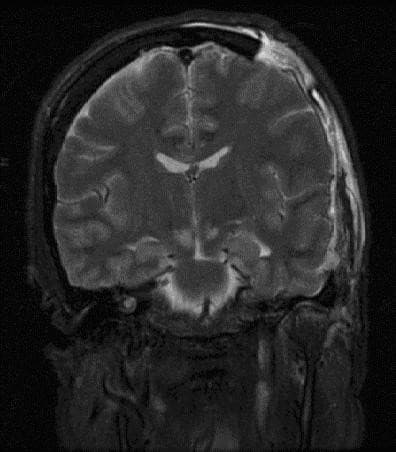

Intracranial pressure (ICP) is the pressure exerted by fluids such as cerebrospinal fluid (CSF) inside the skull and on the brain tissue. ICP is measured in millimeters of mercury (mmHg) and at rest, is normally 7–15 mmHg for a supine adult. The body has various mechanisms by which it keeps the ICP stable, with CSF pressures varying by about 1 mmHg in normal adults through shifts in production and absorption of CSF. Changes in ICP are attributed to volume changes in one or more of the constituents contained in the cranium. CSF pressure has been shown to be influenced by abrupt changes in intrathoracic pressure during coughing (which is induced by contraction of the diaphragm and abdominal wall muscles, the latter of which also increases intra-abdominal pressure), the valsalva maneuver, and communication with the vasculature (venous and arterial systems). Intracranial hypertension (IH), also called increased ICP (IICP) or raised intracranial pressure (RICP), is elevation of the pressure in the cranium. ICP is normally 7–15 mm Hg; at 20–25 mm Hg, the upper limit of normal, treatment to reduce ICP may be needed. In general, symptoms and signs that suggest a rise in ICP include headache, vomiting without nausea, ocular palsies, altered level of consciousness, back pain, and papilledema. If papilledema is protracted, it may lead to visual disturbances, optic atrophy, and eventually blindness. The headache is classically a morning headache that may wake the person up. The brain is relatively poorly supplied by oxygen as a result of mild hypoventilation during the sleeping hours leading to hypercapnia and vasodilation. Cerebral edema may worsen during the night due to the lying position. The headache is worse on coughing, sneezing, or bending and progressively worsens over time. There may also be personality or behavioral changes. In addition to the above, if mass effect is present with resulting displacement of brain tissue, additional signs may include pupillary dilatation, abducens palsies, and Cushing's triad.